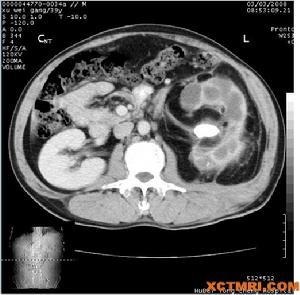

腎周圍炎 CT表現5、一小時尿沉渣計數白細胞>20個;

10、CT最有價值,可顯示腎周軟組織塊,中心CT值0~20Hu,具有一個炎性的壁層,增強後壁層被強化鄰近組織層次不清。腎周筋膜變厚在膿腫中可見到氣體或氣液平面。